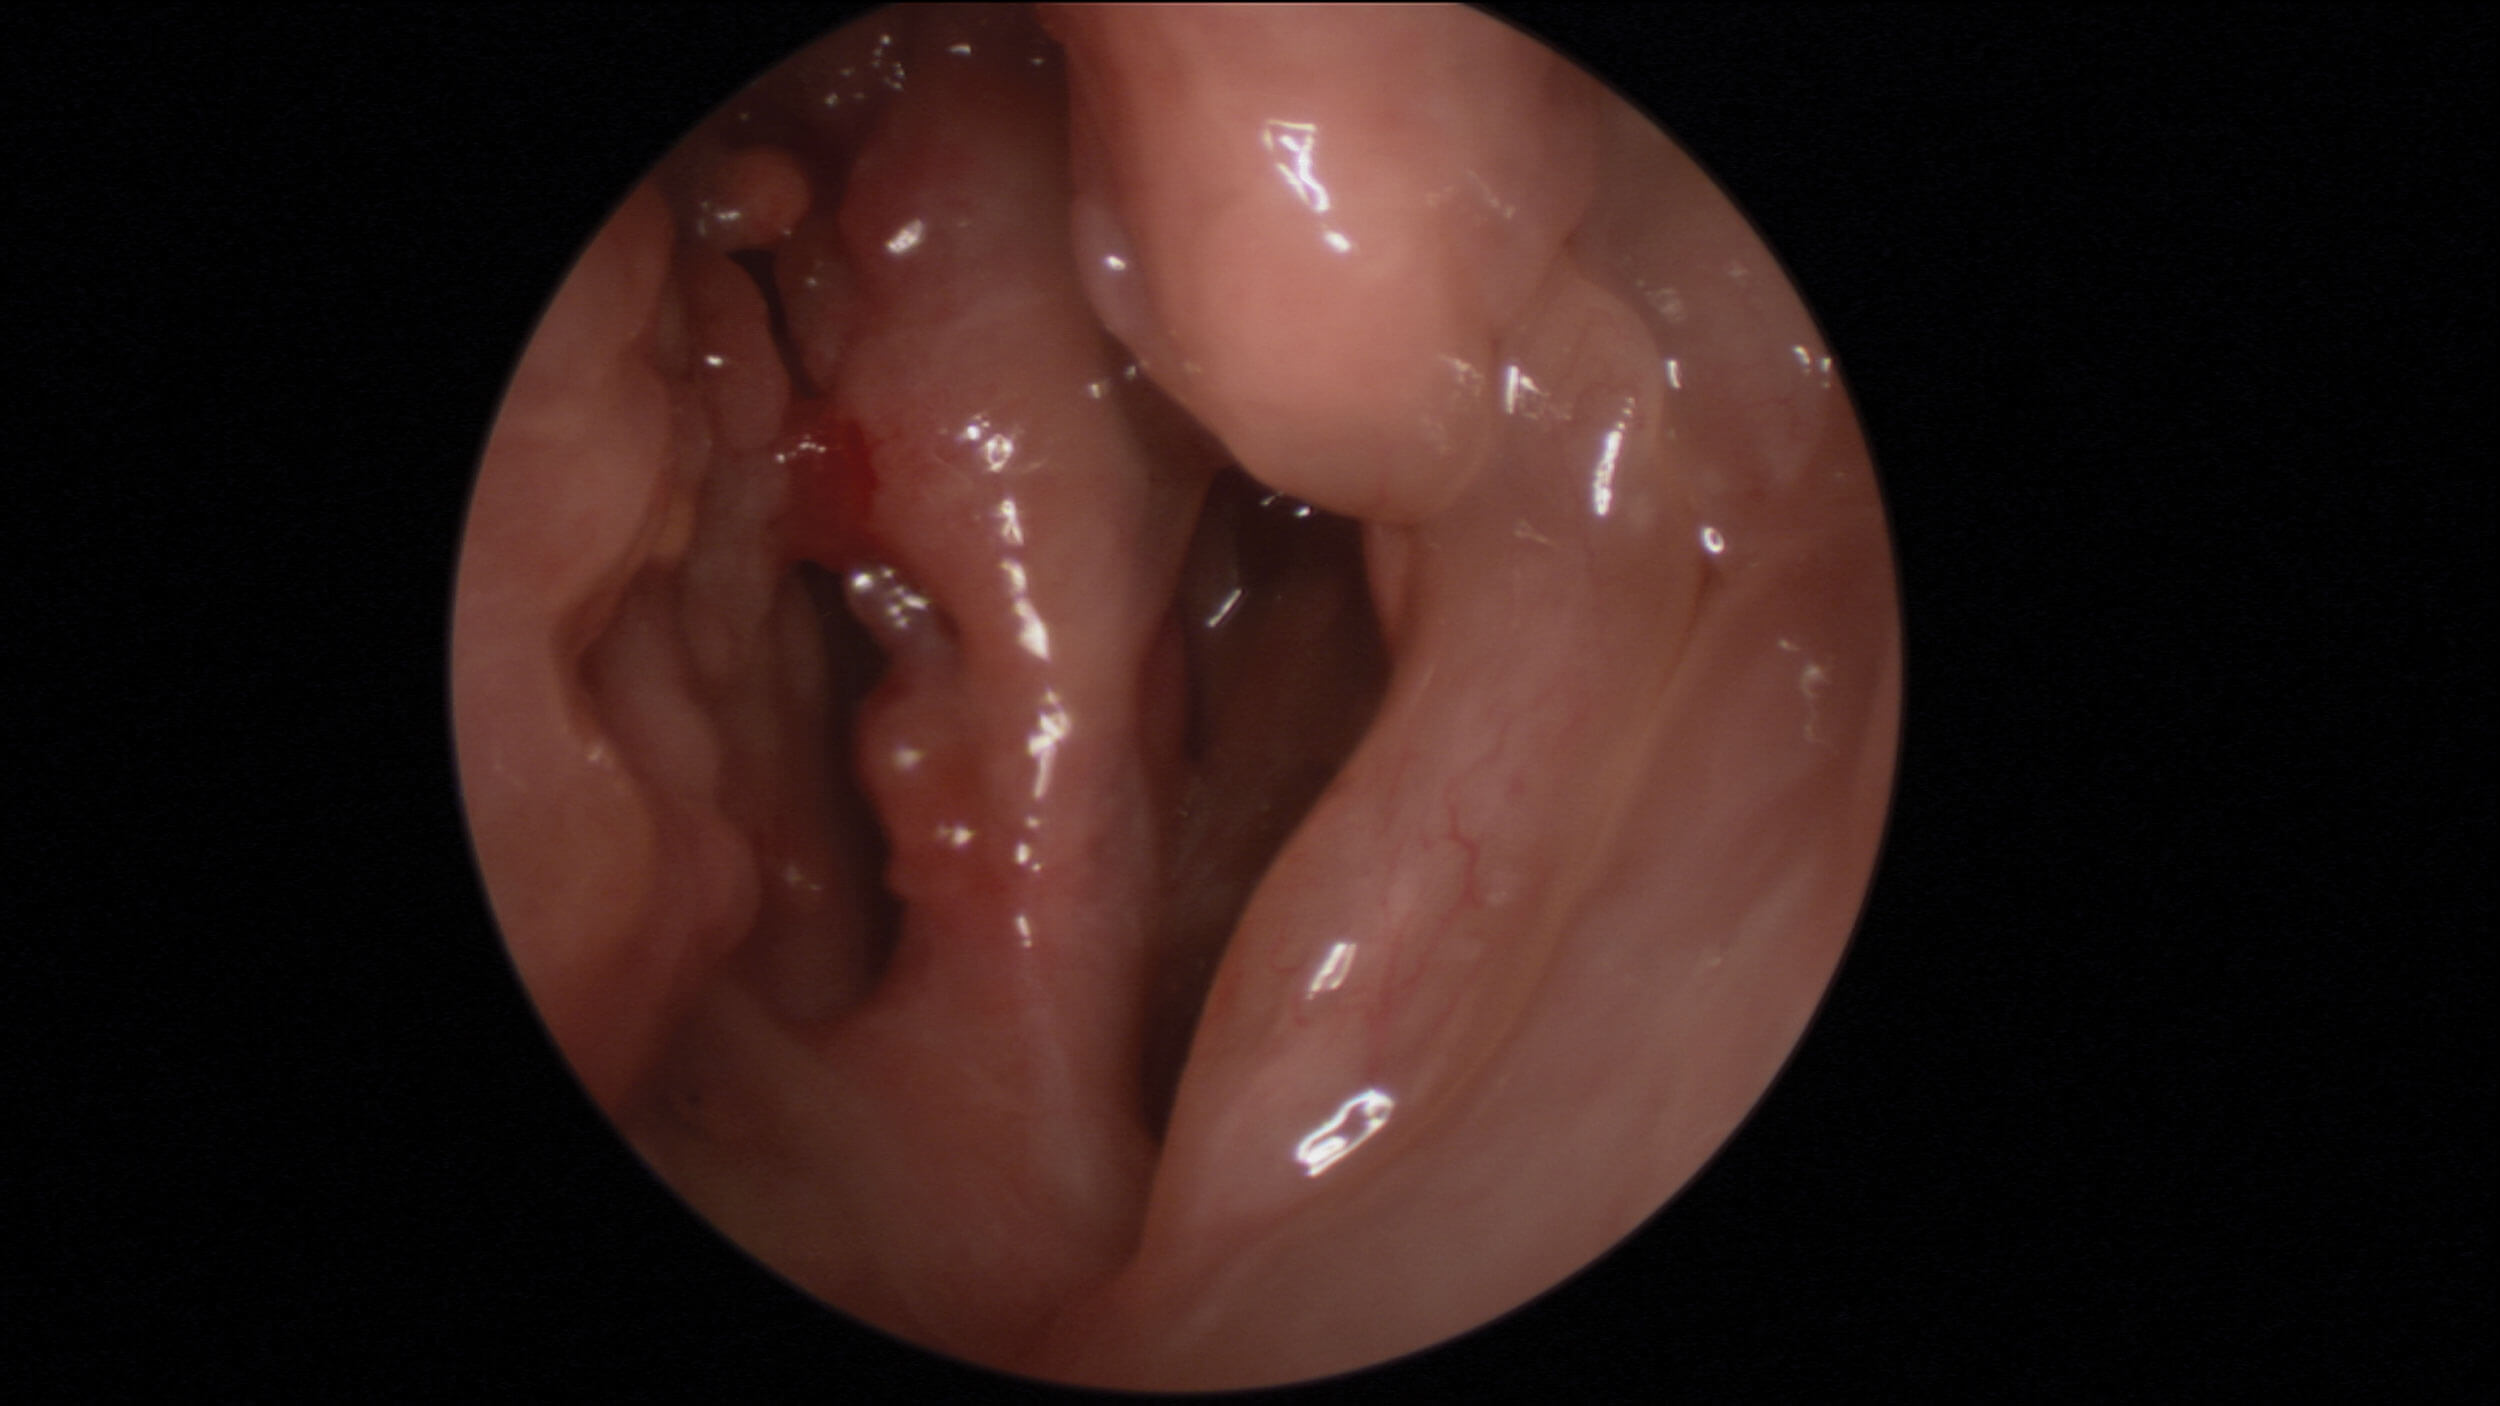

Oedematous olfactory cleft in NERD patient.

Supporting the notion that transmission to the OC due to mucosal oedema or polyps reduces quantitative olfaction is the positive response to oral and nasal steroids in many cases [1]. Furthermore, opacification of the olfactory cleft, as demonstrated on paranasal sinus CT imaging, has been shown to correlate well with olfactory function on psychophysical testing [2]. But it is not just oedematous mucosa that can occlude the olfactory clefts; thick eosinophilic mucin as seen in cases of non-steroidal exacerbated respiratory disease (NERD) and allergic fungal rhinosinusitis (AFRS) that can also accumulate in the olfactory clefts and spheno-ethmoidal recesses.